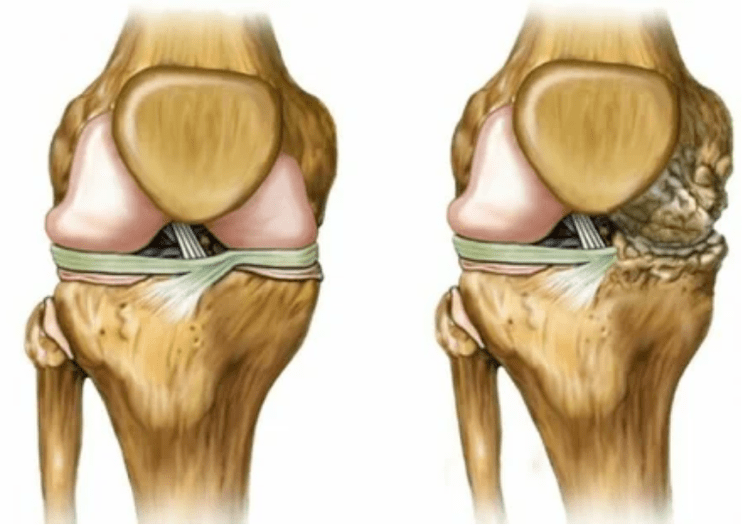

- Fase 2. Vanwege het aanbodgebrek worden de benodigde cartridges vernietigd, worden botgroei gevormd op het oppervlak van het kraakbeen. De pijnen verwerven een meer uitgesproken karakter, intensiveren na een lange rust, worden geëlimineerd door kleine fysieke arbeid. Pijn gaat gepaard met ontsteking. De spieren zijn uitgerekt, wat leidt tot zwakke of gemiddelde verminderde motorfuncties.

- 3 graad. Vaak zijn er pijnen, het is moeilijk om het ledemaat te verplaatsen vanwege veranderingen in het gewricht. De laesies zijn uitgebreid, worden merkbaar voor de naakte look. De vervorming van de gezamenlijke site treedt op, het getroffen gebied zwelt op en wordt rood. De ledemaatas is verstoord, wat leidt tot de complexiteit van beweging. Pathologische veranderingen veroorzaken het verkorten van de ligamenten. Subbsuzen en contracturen verschijnen. De aangrenzende spieren worden ingekort of uitgerekt, waaruit de contractiele functie is verzwakt.